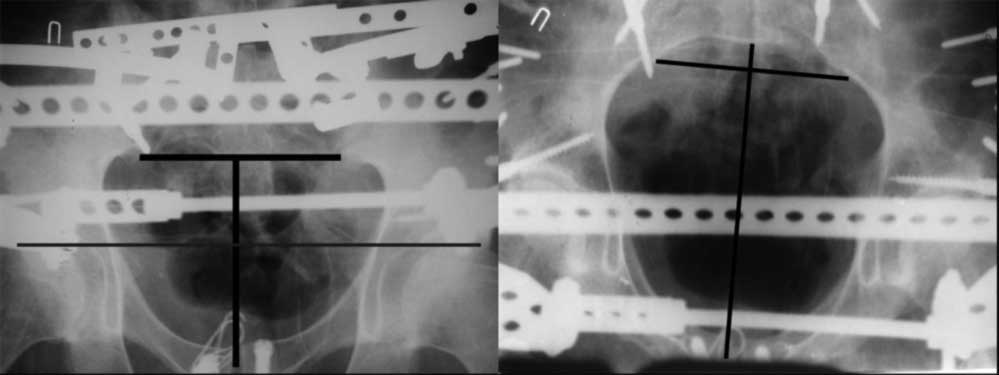

закрытое низведение правой половины таза кольцевым аппаратом (с

фиксацией задних отделов), затем проведение илиосакральных винтов,

реостеосинтез лонного сочленнения, дальнейшая фиксация в аппрате 2-3

мес. Похожий пример в приложении.